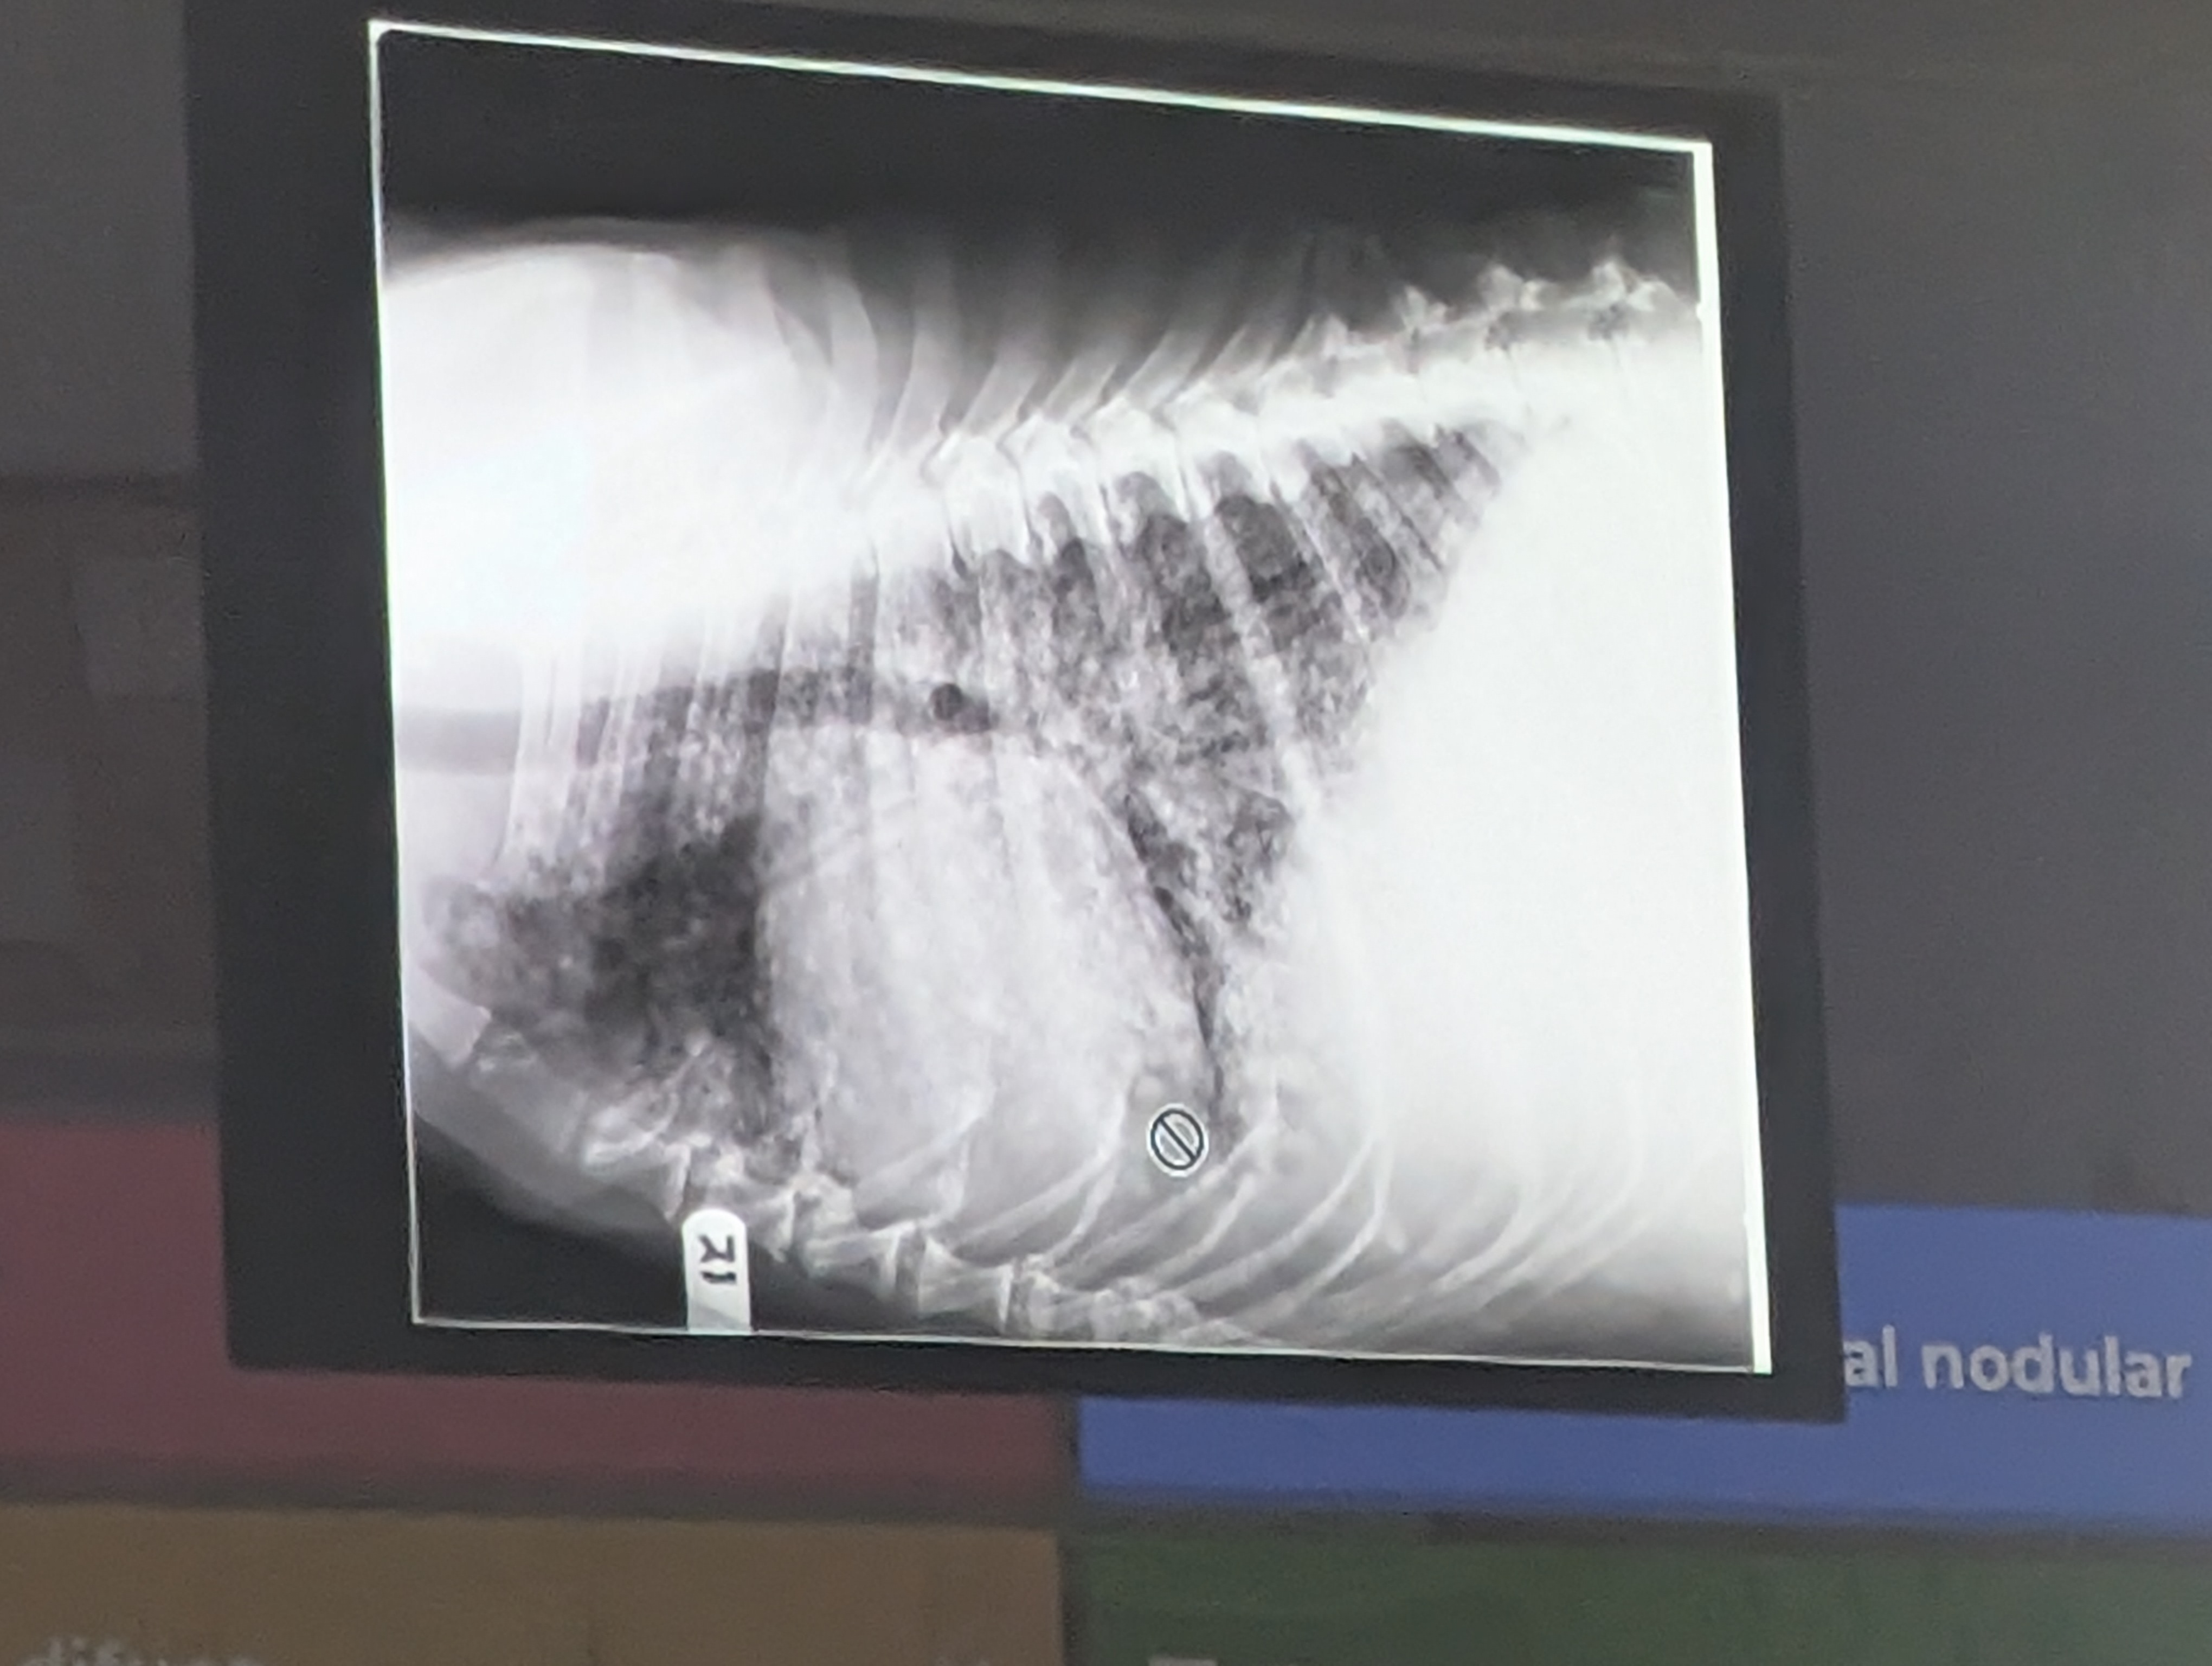

3) Una respuesta correcta

- patron vascular (Puntitos radiopacos por donde los vasos)

- Cardiomegalia (Corazón agrandado)

- Patron intersticial difuso (Falta radiolucidez en general)